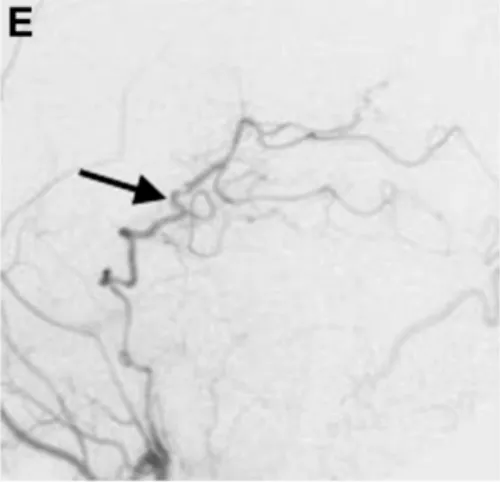

術(shù)后1周復(fù)查頸外動脈血管造影顯示,通過新建的分流血管,左側(cè)大腦后動脈供血區(qū)血流完全通暢(圖E箭頭標(biāo)注),沒有出現(xiàn)任何缺血跡象。

術(shù)后1周頸外動脈血管造影顯示,通過分流血管,整個左側(cè)大腦后動脈供血區(qū)血流良好(箭頭標(biāo)注)。